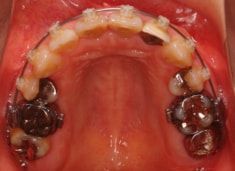

治療前